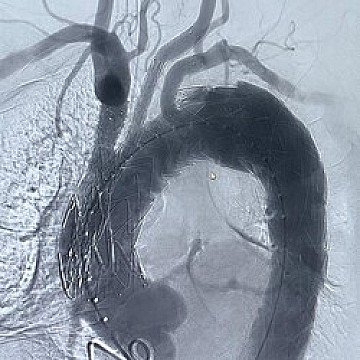

Según los especialistas, la patología de la aorta compleja es grave y su tratamiento consume gran cantidad de recursos. Afortunadamente, no es de las más frecuentes, pero su prevalencia va en aumento, tanto por el empleo generalizado de pruebas de imagen, como por el envejecimiento de la población. No obstante, el síndrome aórtico agudo y la disección aórtica afectan a un subgrupo de pacientes más jóvenes. En concreto, se estima una incidencia aproximada de tres casos por 100.000 habitantes/año para la disección aórtica aguda y de seis casos por 100.000 habitantes/año para aneurismas toracoabdominales.

En el simposio, los expertos cubren el tratamiento de forma integral, incluyendo el arco aórtico y la aorta yuxta o pararrenal y toracoabdominal, tanto desde el punto de vista endovascular, como a través de la cirugía abierta, ya que hay un significativo número casos donde esta última es la mejor opción. No obstante, en el ámbito endovascular, los especialistas afirman que el mayor desarrollo se ha dado en las nuevas endoprótesis fenestradas, endoprótesis con ramas y con fenestraciones precanuladas que facilitan el tratamiento de estos casos. “La cirugía abierta sigue siendo el tratamiento de elección para la resolución de la patología del arco aórtico; solo en casos de alto riesgo se pueden emplear otras opciones. Sin embargo, se ha avanzado mucho en técnicas menos invasivas. El avance más importante es la utilización de procedimientos híbridos (cirugía más endoprótesis en el mismo acto quirúrgico), que simplifican la intervención, la protección cerebral y de otros órganos, y el manejo postoperatorio. Con estos cambios, hemos mejorado mucho los resultados hoy en día”, detalla el Dr. Silva.